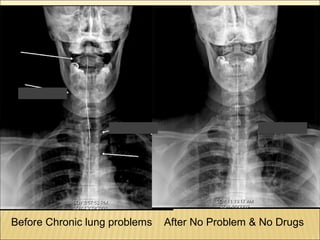

22. Before Chronic lung problems After No Problem & No Drugs